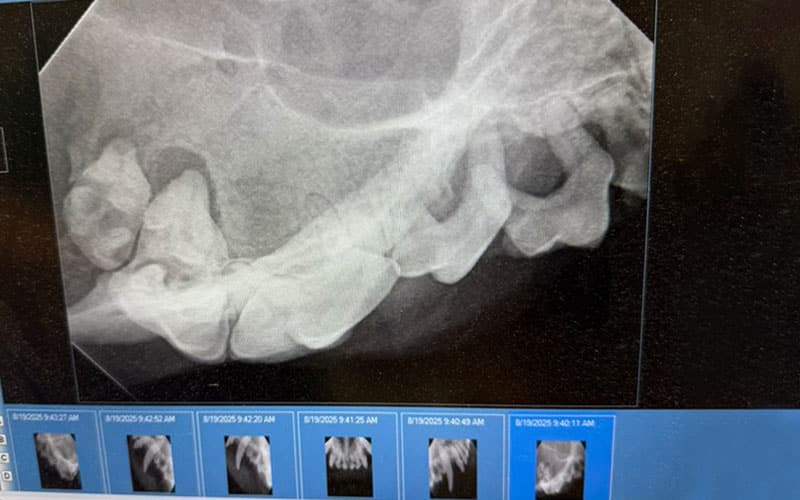

Dentistry/Oral Surgery

Many dental problems require surgical intervention to remove diseased teeth. Our veterinary team can perform a range of dental procedures to address complex dental issues, including oral tumors. We use oral nerve blocks and injectable pain medications to ensure your pet remains comfortable throughout their stay. We send each pet home with personalized recommendations for home care and follow-up.